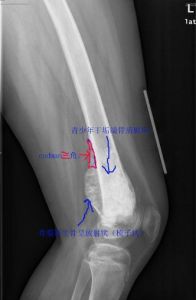

X線片表現

骨質緻密度不一。有不規則的破壞,表面模糊,界限不清,病變多起於骺端,因腫瘤生長及骨膜反應高起形成考德曼氏三角,有與骨幹垂直方向的放射形骨針。

1.肉眼所見腫瘤發生在髓腔並在髓腔內擴張和破壞與穿破骨皮質進入軟組織。腫瘤因發生部位不同而形狀不一,腫瘤切面可因細胞成分不同而色彩及質地各異,灰白色、質軟、魚肉樣,藍白色、質脆、軟骨樣,灰白色、質韌、橡皮樣和堅如象牙的瘤骨,壞死及出血區為灰黃色和紅褐色分布在腫瘤之間。腫瘤偏於某側被穿破的骨皮質無膨脹,骨膜被掀起可見三角形骨膜反應。